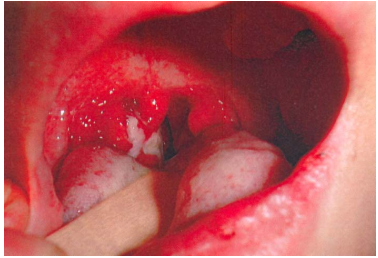

3 一位 8 歲男童發燒、咽喉痛 3 天,上眼皮有浮腫現象,眼睛未發紅亦無分泌物,咽部如圖所示。給 予 amoxicillin 40 mg/kg/day q8h,3 天之後仍未退燒,全身出現許多針頭至米粒大小的紅色丘疹。下 列那一項是最可能的診斷?

(A)Kawasaki disease (B)scarlet fever (C)pharyngoconjunctival fever (D)infectious mononucleosis

4 (A)echocardiogram (B)throat bacteria culture (C)anti-streptolysin O titer (D)rickettsia antibody

5 承上題,在還沒有檢查結果之前,可以給予下列那一種口服藥物? (A)Aspirin (B)vitamin B (C)steroid (D)zinc supplement